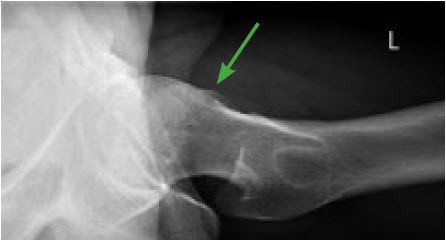

Darüber hinaus gibt heute eine Reihe von klinischen Tests, die Diagnose zu sichern. Ein Röntgenbild in zwei Projektionen wird immer erstellt, um die Form des Gelenkkopfs und der Gelenkpfanne zu beurteilen. In der Regel wird zusätzlich eine Magnetresonanztomografie (MRI-Untersuchung) mit Kontrastmittel durchgeführt, wodurch Veränderungen im Gelenk und an den Weichteilen gut dargestellt werden können. Sollten die Befunde nicht eindeutig sein, so muss auch an andere Ursachen wie eine Muskelzerrung, einen Leistenbruch oder eine Rückenproblematik gedacht werden. Eine unter Durchleuchtungskontrolle durchgeführte Betäubung (Infiltration) des Hüftgelenks kann zusätzliche Sicherheit bei der Differenzierung zwischen Gelenkschmerz und anderer Schmerzursache geben. Weiter kann ein Ultraschall der Leiste in der Diagnosesicherung hilfreich sein und allenfalls einen Leistenbruch bestätigen oder ausschliessen. Auch können mehrere Diagnosen gleichzeitig vorliegen.